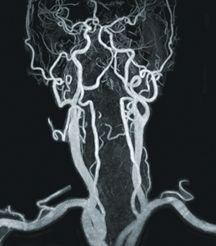

High-resolution CE-MRA carotids using Philips Sense and Centra.

MRA Breaks into Multiphase Imaging

One benefit of MRA is that it is a noninvasive procedure, using magnetic resonance instead of radiation. Although it requires contrast material, it is gadolinium-based — much safer than others and is used in much smaller doses.

Like CTA, MRA has the ability to acquire 3-D images, but within the last three or four years, MRA has begun doing multiphase imaging, a method unique to MR. Multiphase imaging takes repeated images of an area as the contrast material travels through the veins. This is difficult to do with CTA because it would have to continually repeat X-rays, and there would be a risk with the radiation dose. Clarkson explained that this could be particularly useful in studies of the lower legs where blood flow to one leg is slower than the other. With multiphase imaging, the radiologist can look at the blood flow over time, and if one leg is slower than the other, a scan can be done so there is never an image where the vasculature is unclear. MRA is also becoming faster, eliminating CTA’s spatial resolution advantage.